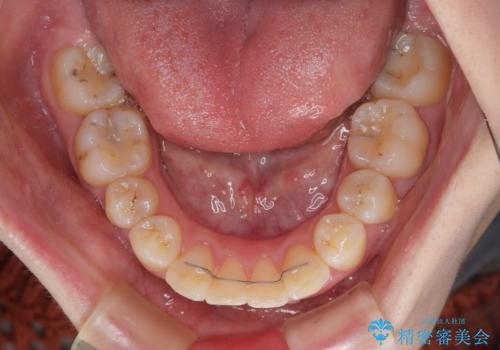

飛び出した前歯 抜歯矯正で横顔が劇的変化

- 飛び出した上顎前歯を気にして来院された患者様です。

下顎は左右2番目の歯が2本欠損しており、上下前歯の前後的な位置は著しくずれている状態でした。

骨格的にも上顎骨が前突傾向にあり、極端な過蓋咬合になっていました。

強い咬合力に抵抗するように歯を動かす必要があるにもかかわらず、上顎第一大臼歯が1本欠損しているため、治療は困難を極めることが予想されました。